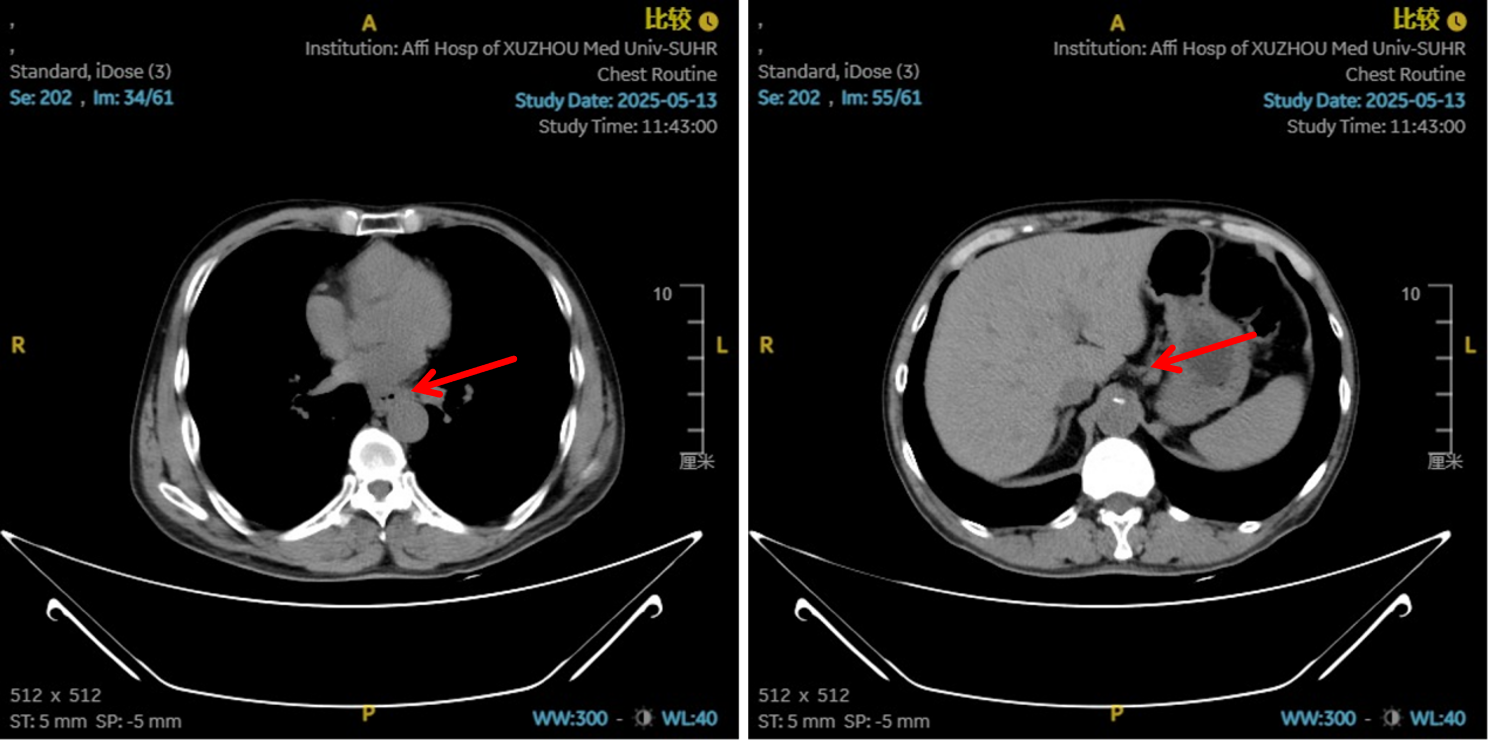

图3:2 周期化疗联合抗血管治疗后淋巴结对比

图4:2周期治疗后影像学 [图左:“食管Ca化疗后”,食管胸中下段管壁增厚,较厚处管壁约15mm,边缘模糊,病灶局部与邻近大血管、气管壁分界不清。图右:纵隔内(3P、4、7)、左肺门及胃小弯旁示多发稍大、增大淋巴结影,部分融合,较大者大小约16mmx13mm。]

图6:4、6周期化免靶后淋巴结对比

图7:4周期治疗后影像学 [图左:“食管Ca化疗后”,食管胸中下段管壁增厚,较厚处管壁约12mm,边缘模糊,病灶局部与邻近大血管、气管壁分界不清。图右:纵隔内(3P、4、7)、左肺门示稍大淋巴结影。]

疗效评估

治疗2周期后,食管壁厚度由17mm降至15mm,淋巴结由18mm×15mm缩小至16mm×13mm;4周期后,食管壁进一步缩至12mm,淋巴结明显减少;6周期后,食管壁仅余10mm,纵隔内仅见小淋巴结影,疗效评估“接近CR”。